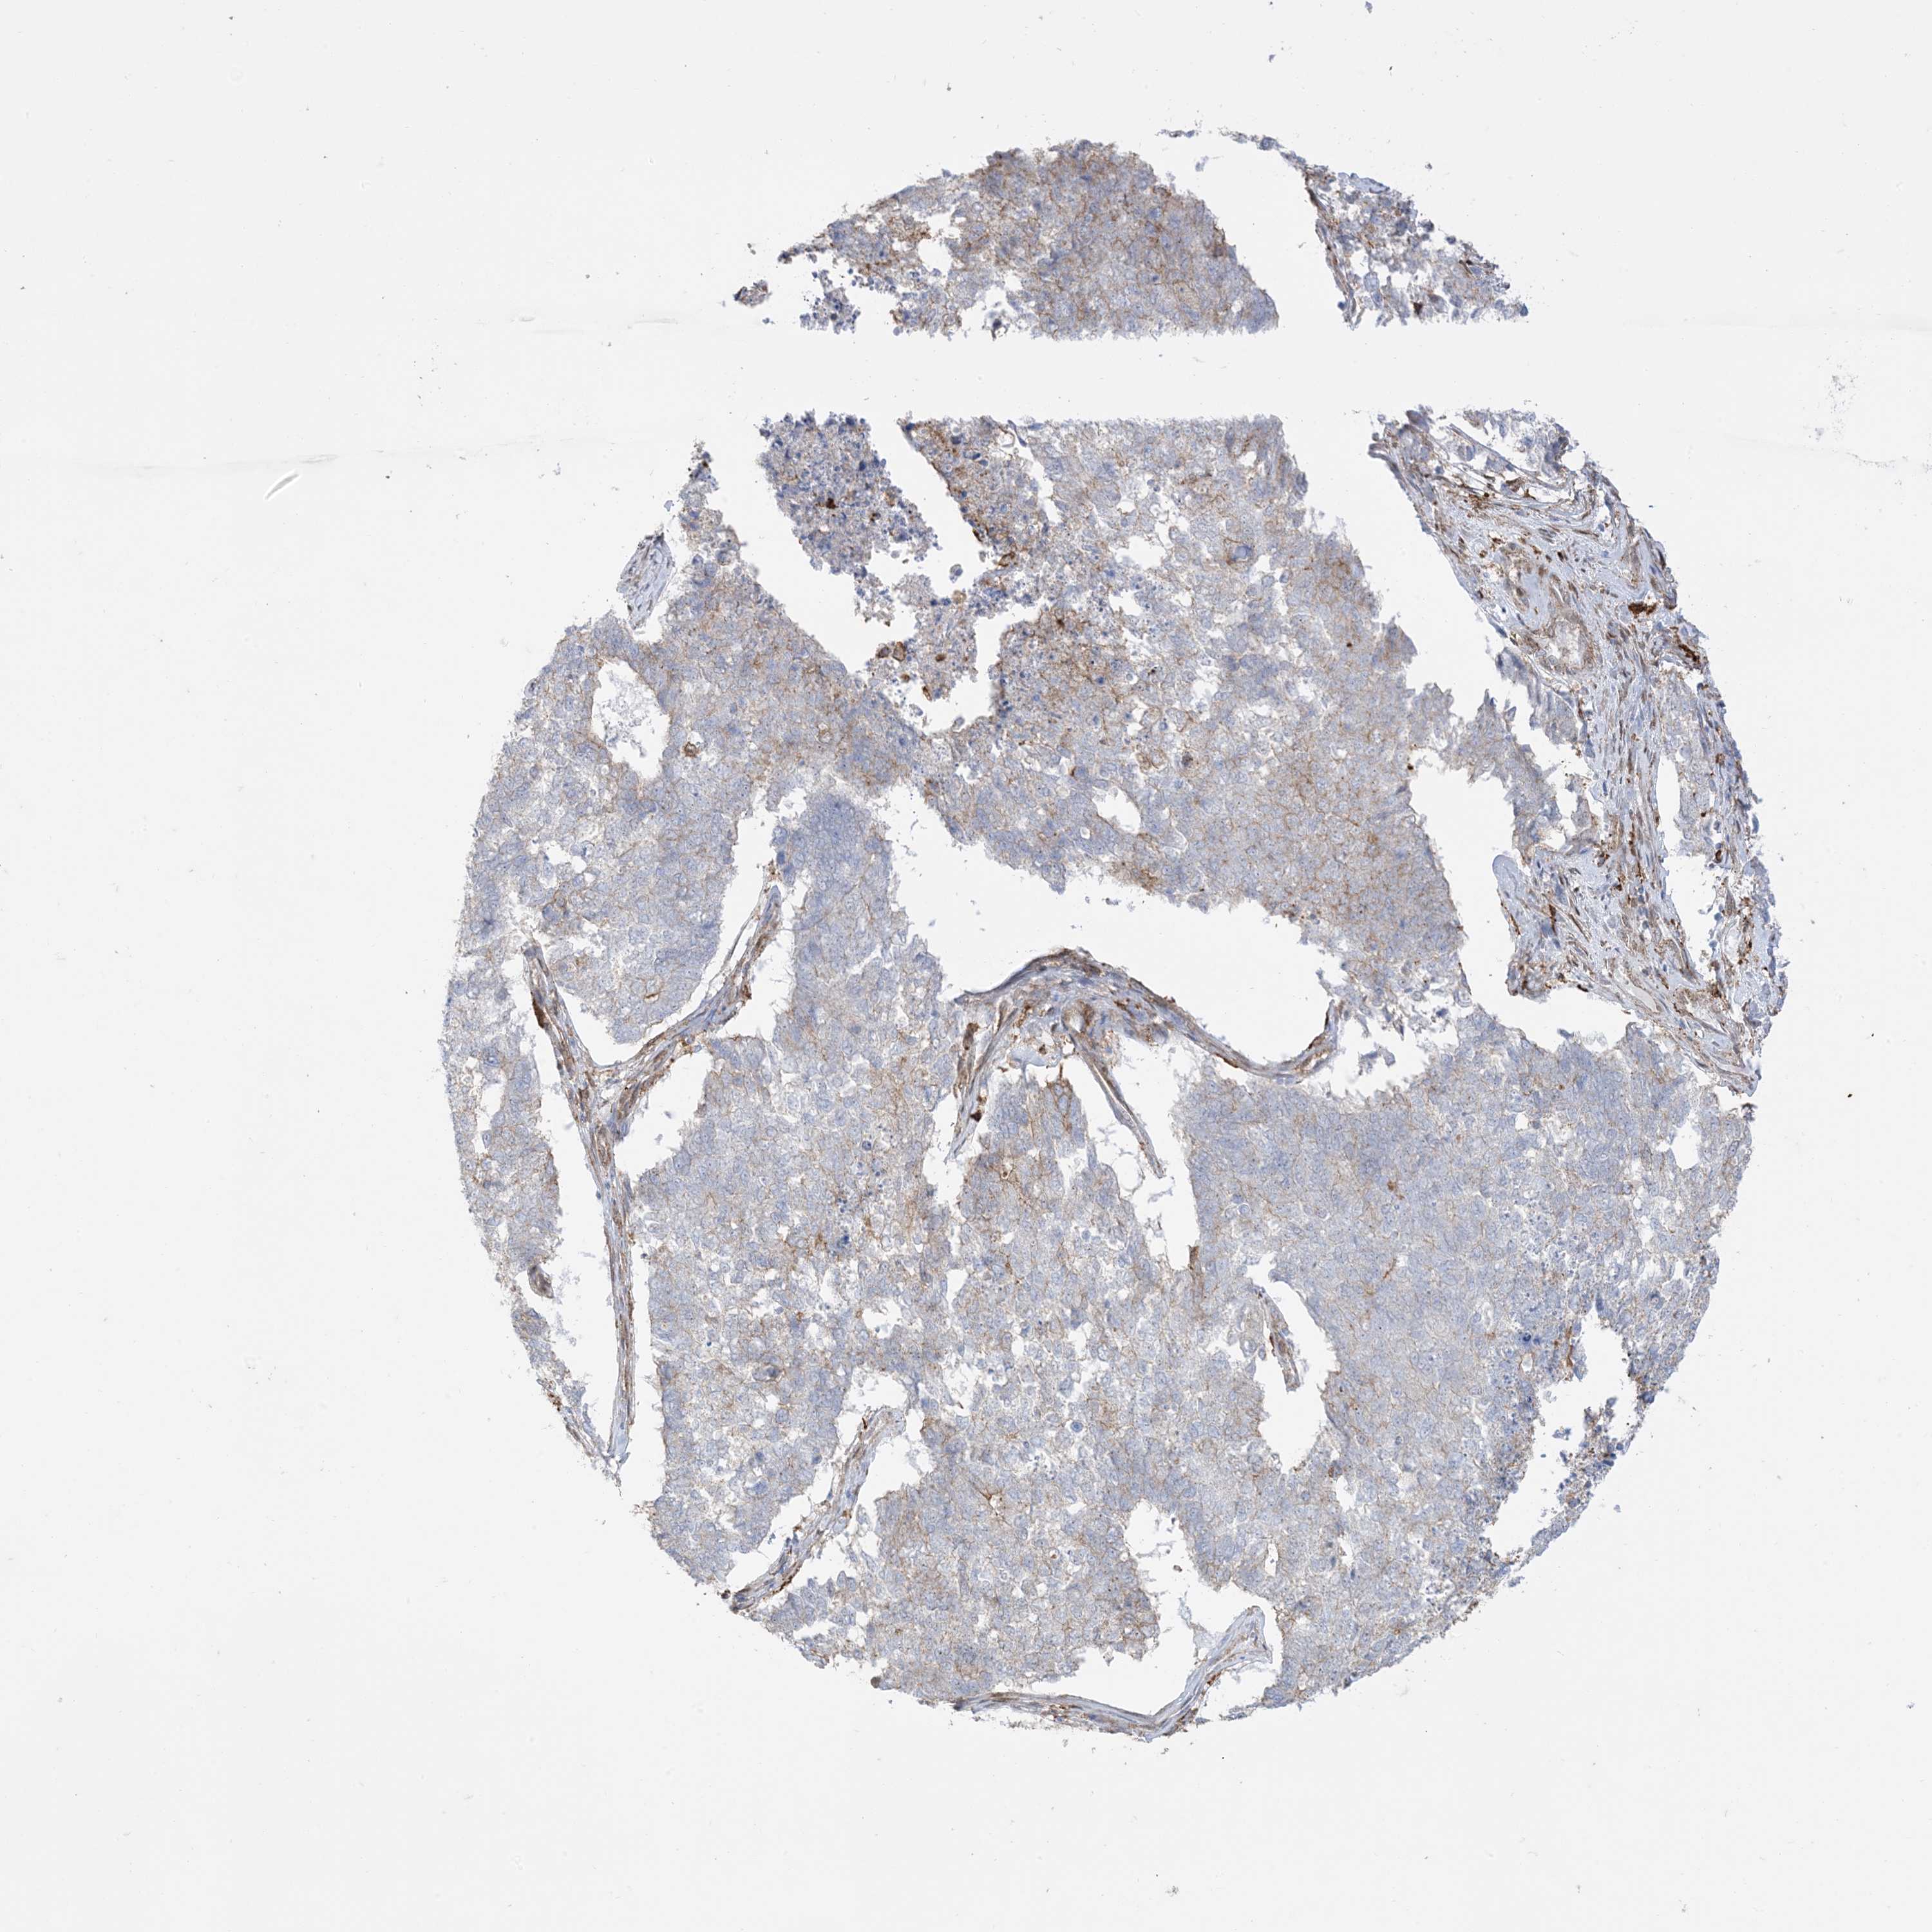

CERVICAL CANCER - Protein expressioni

A mouse-over function shows sample information and annotation data. Click on an image to view it in a full screen mode. Samples can be filtered based on level of antibody staining by selecting one or several of the following categories: high, medium, low and not detected. The assay and annotation is described here.

Note that samples used for immunohistochemistry by the Human Protein Atlas do not correspond to samples in the TCGA dataset.

Antibody stainingi

Antibody staining in the annotated cell types in the current human tissue is reported as not detected, low, medium, or high, based on conventional immunohistochemistry profiling in selected tissues. This score is based on the combination of the staining intensity and fraction of stained cells.

Each image is clickable and will lead to virtual microscopy that enables deeper exploration of all samples and also displays staining intensity scores, fraction scores and subcellular localization as well as patient and tissue information for each sample.

Antibody HPA054026

Antibody CAB010823

Antibody CAB016728

Antibody CAB036009

Squamous cell carcinoma, NOS